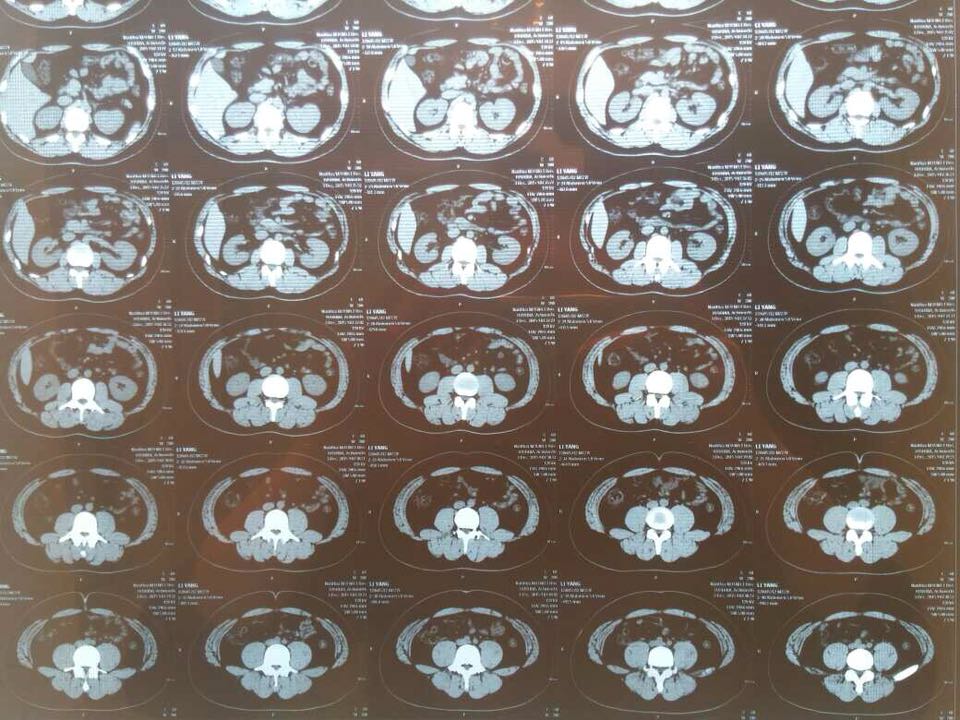

23岁男性,二十天前无明显诱因左下腹痛,疼痛为间歇性酸痛,胀痛,腹痛位于髂脊内侧,有轻度肌紧张、压痛,间歇性发作,无明显加重,休息后可缓解,大小便可,有腰椎间盘突出病史,现ct如上,ct示:小肠左侧集中,肠系膜粘连?。消化道造影示:小肠粘膜光滑,未见明显异常。全腹彩超,血常规,尿常规未见明显异常。无恶心,呕吐,便秘,消瘦等症状,怎么考虑?